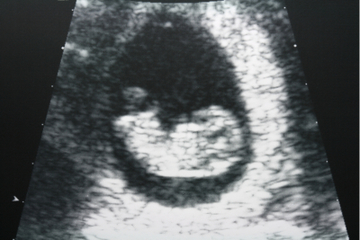

妊娠8週になると、胎芽は人の形に近づき胎児へと呼び名が変化します。胎嚢の大きさは3cm前後となり、赤ちゃんが手足を動かしたり羊水を飲んだりする動作が見られるようになります。

超音波検査で見られる画像にかわいさが募る反面、ママのつわりはピークを迎え体調面で困難なことも出てくるかもしれません。大きくなりはじめた子宮に膀胱や腸が圧迫されるため、トイレが近くなったり便秘になったりという症状も見られます。